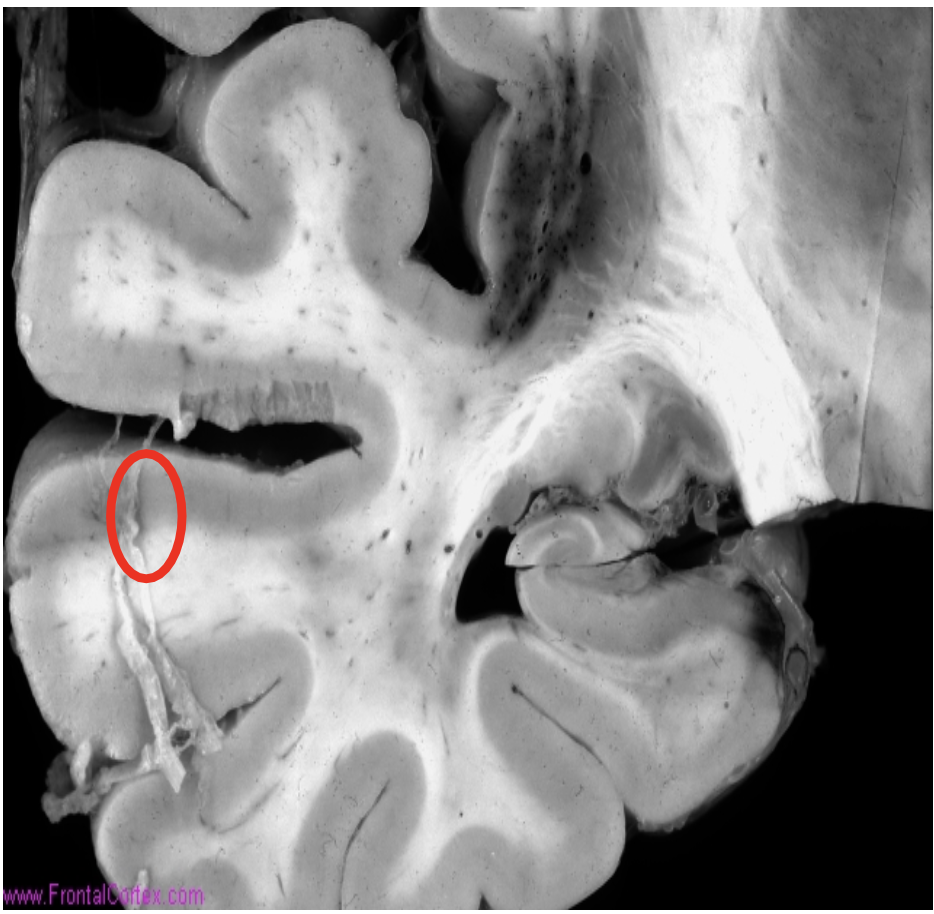

Lacunar infarcts

Infarctions ranging in size from 1 mm to 1.5 cm (arrow)

Classically, the walls of small arteries become thickened from the formation of hyaline membranes (lipohyalinosis) (circle)

-Caused by chronic hypertension.

-These arteries may also rupture.